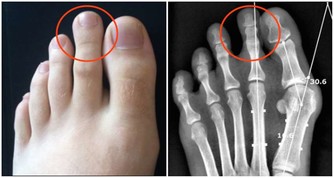

露腳踝易得踝關節炎現在很多年輕人把捲起褲腿或者穿短襪露出白皙纖細的腳腕當成一種時尚。但在醫生看來,這種看似時尚的穿著,最容易誘發踝關節炎。

東南大學附屬中大醫院中醫骨傷科主任屈留新解釋,腳踝部位分布著淋巴管、血管、神經等近十個重要的組織,被稱為人體的第二心臟,如果經常把腳踝露出來,不僅會引發踝關節炎,還會使抗病能力下降而導致感冒。

另外,東南大學附屬中大醫院中醫骨科副主任醫師陸軍說,腳踝承受著全身的重量,是人體比較脆弱的地方,對外傷缺乏緩衝,很容易受到各種傷害。再加上踝關節周圍軟組織少,局部血液循環較差,如果再不穿襪子加以保護,很容易著涼而引發疾病。而能不能露腳踝,還要看個人體質,不要盲目去效仿。